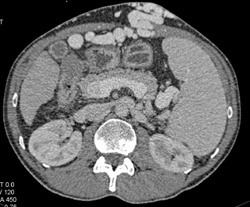

Carcinoid With Implants in the Liver